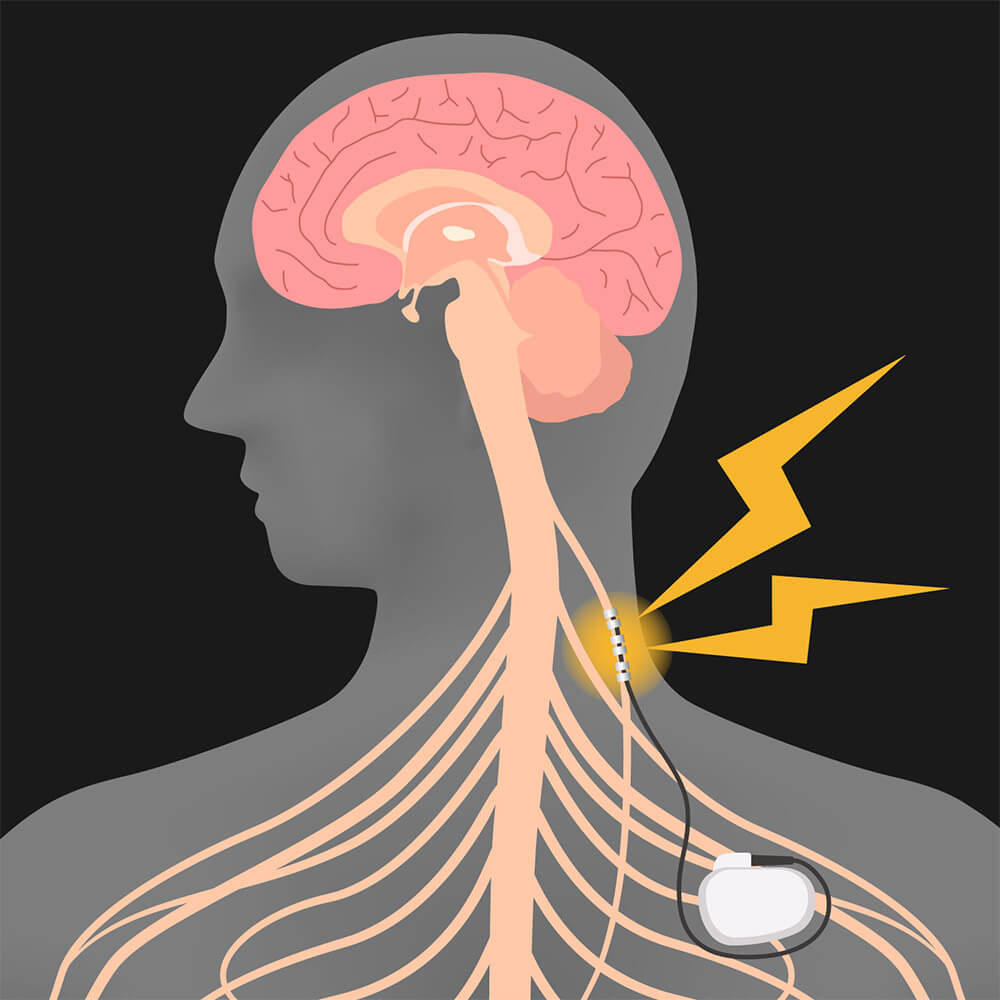

Sonuçta, yüksek yağ içerikli-yüksek karbonhidratlı çöp gıdalardan oluşan “kafeterya diyetinin” vagus sinirinizin duyarlılığını azaltarak obezojenik olduğunu biliyoruz. Yine mevcut çalışmalarda, vagus siniri uyarımının bunu geri çevirdiğini ve kiloda ciddi düşüşe yol açtığını, ancak, bu cihazın cerrahi olarak vücuda implante edilmesi gerektiğinden evinizde yapabileceğiniz uygulamalar olduğunu biliyoruz. Ya da şimdiye kadar böyleydi 🙂 Evinizde uygulayabileceğiniz vagal stimulasyon terapisi için +447918548789 nolu Whatsapp numarasından bize ulaşabilirsiniz. Vagustim metodu ile ilgili daha fazla bilgi için bize yazabilirsiniz.